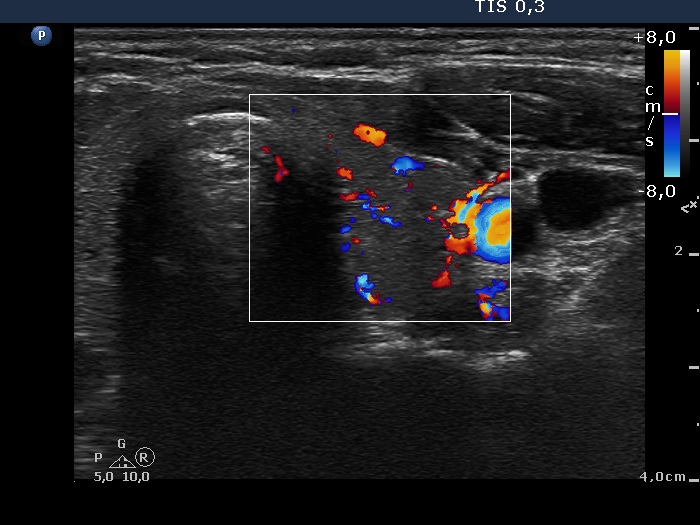

First examination (1st row of images)

Clinical data: A 29-year-old woman requested a second opinion. She was treated for Graves' disease for 2 months. The TSAb was initially 8.9 U/L, the FT4 was 54.2 pM/l. She get 30 mg methimazole therapy. Her complaints have already decreased.

Palpation: no abnormality.

Results of blood test: hyperthyroidism - TSH undetectable, FT4 29.2 pM/L, FT3 8.91 pM/L.

Ultrasonography: The thyroid was minimally enlarged and moderately hypoechogenic. The vascularization was a bit increased.

The dose of methimazole was reduced to daily 15 mg.